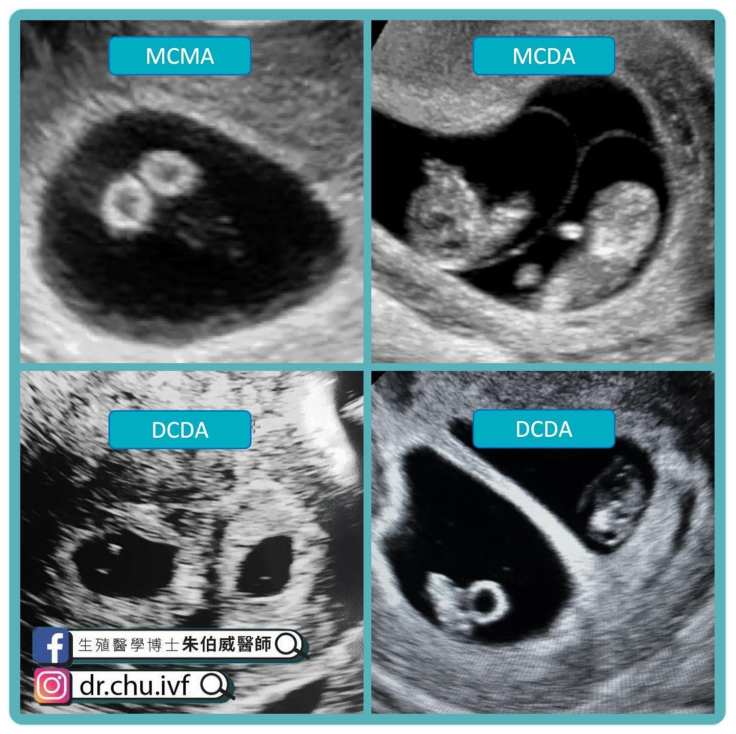

我的雙胞胎寶寶是同卵還是異卵?

如果你是單絨毛膜的雙胞胎

就一定是同卵

但如果是雙絨毛膜

就可能是同卵或是異卵

絨毛膜一個還是兩個比同卵異卵對我們更重要

因為絨毛膜一個或是兩個就代表胎盤是一個或是兩個

胎盤共用跟胎盤各自獨立可能產生的問題跟追蹤重點都不一樣